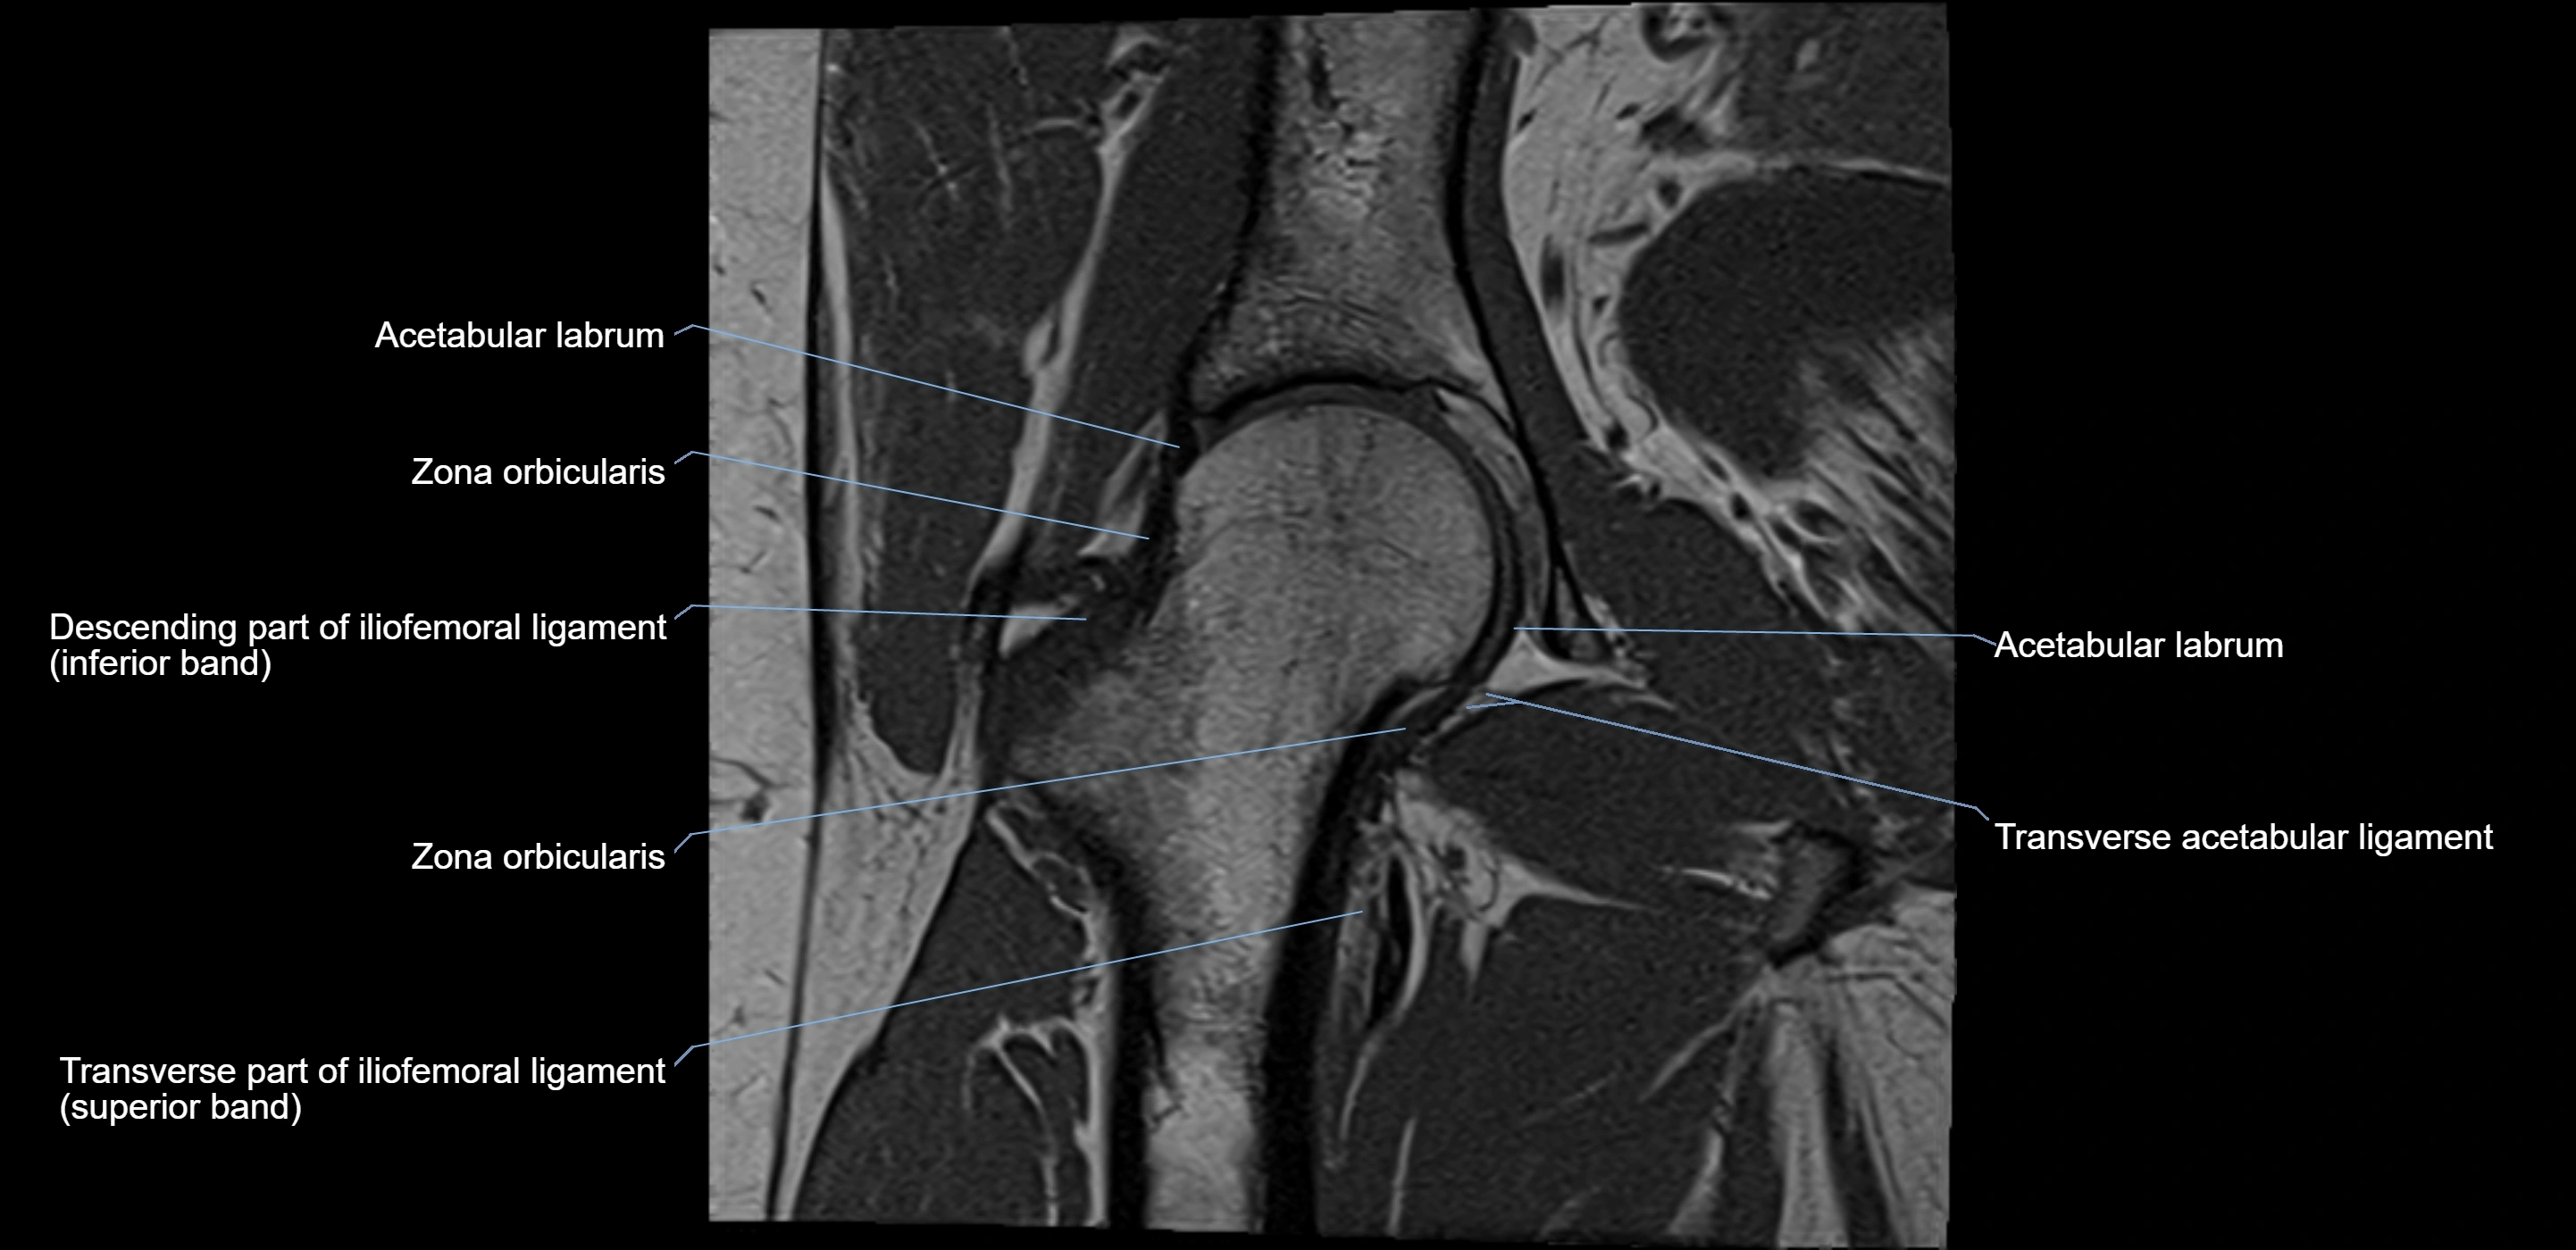

The acetabular labrum is a fibrocartilaginous ring that surrounds the rim of the acetabulum in the hip joint. It deepens the hip socket, increases joint stability, and maintains a suction seal that preserves negative intra-articular pressure. Structurally, the labrum transitions from hyaline cartilage of the acetabulum to dense fibrocartilage at its free edge.

It is triangular in cross-section, with its base attached to the acetabular rim and its apex projecting toward the femoral head. The labrum is most robust superiorly and anteriorly, where load bearing is greatest, and relatively thinner inferiorly.

Structure and Relations

• Superior and anterior labrum: thickest portions, stabilizing against anterior dislocation

• Inferior labrum: blends with the transverse acetabular ligament bridging the acetabular notch

MRI Appearance

T1-weighted images:

• Labrum: low signal intensity (dark)

• Surrounded by intermediate signal joint fluid (bright on arthrogram)

• Tears: linear or focal areas of intermediate-to-high signal interrupting labral continuity

T2-weighted images:

• Joint fluid: bright, making labral tears visible as fluid extending into or around labrum

• Degeneration: may show areas of increased signal within labrum